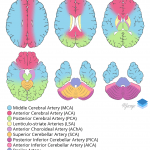

- Areas of hypoattenuation in the right middle cerebellar peduncle and superior cerebellum with loss of gray-white differentiation

- Superior cerebellar artery infarct

Areas of hypoattenuation in the right middle cerebellar peduncle and superior cerebellum with loss of gray-white differentiation are concerning for acute/subacute ischemia in the right superior cerebellar artery distribution. Associated edema with resultant partial effacement of the right ambient cistern. No evidence of hemorrhagic transformation, herniation, or hydrocephalus. Recommend brain MRI for further evaluation.